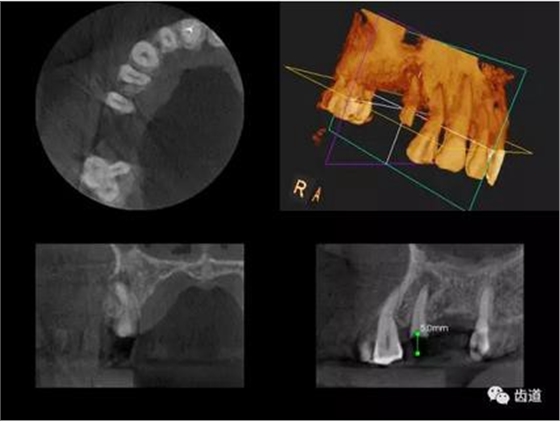

2、下頜磨牙阻生

下頜第二第三磨牙阻生口腔曲面斷層片影像

下頜第二第三磨牙阻生CBCT影像定位

三種圖片的影像學(xué)比較